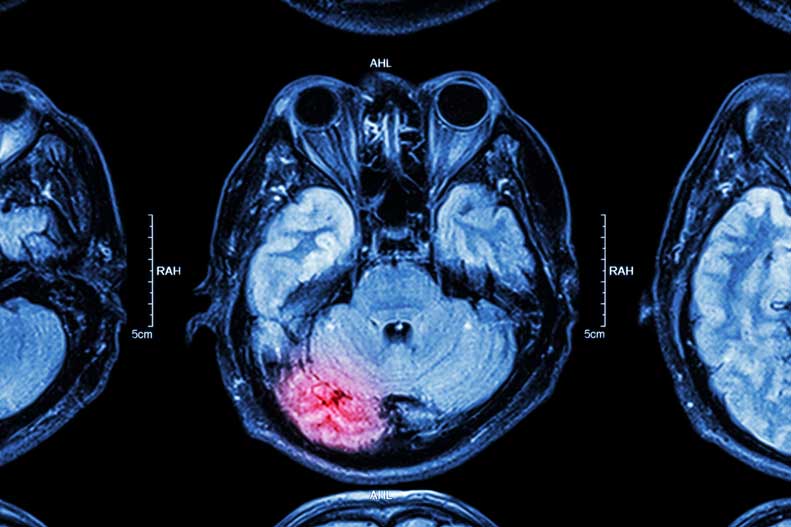

Đột quỵ do thiếu máu cục bộ xảy ra khi mạch máu cung cấp máu lên não bị tắc nghẽn bởi cục máu đông. Đột quỵ xuất huyết xảy ra khi một mạch máu trong não trở nên yếu và vỡ ra, khiến máu chảy vào não. Cả hai loại đột quỵ này có thể gây ra nhiều triệu chứng khác nhau, tùy thuộc vào phần não bị ảnh hưởng, bao gồm:

Mức độ nghiêm trọng và thời gian của các triệu chứng đột quỵ có thể khác nhau ở mỗi người. Nếu bạn nhận thấy bất kỳ dấu hiệu nào trong số những dấu hiệu này ở bản thân hoặc người khác, hãy tìm kiếm sự chăm sóc y tế ngay lập tức. Các biện pháp can thiệp bằng thuốc và phẫu thuật có thể giúp điều trị đột quỵ và tăng tỷ lệ sống sót và hồi phục.